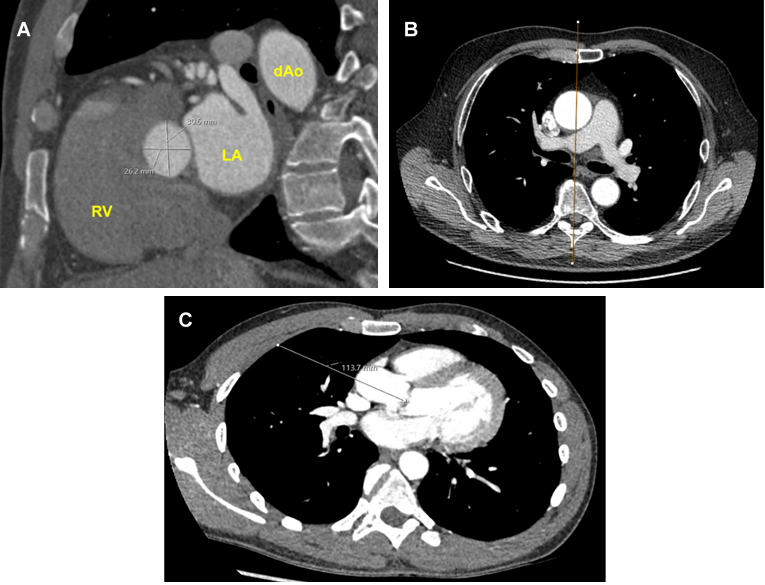

1. Aortic valve annulus sizing. The minimum and maximum annulus diameter are both greater than 20mm (Figure 2a).

2. More than one half of the ascending aorta is located rightward of the right sternal border at the level of the main pulmonary artery (Figure 2b).

3. Distance from the mid-clavicular line of the second intercostal space to the aortic valve is less than 120mm (Figure 2c).

Figure 2. Pre-operative CT imaging measurements. A: Aortic annulus sizing; B: Rightward ascending aorta; C: Distance from second intercostal space to aortic valve.

RV = Right ventricle; LA = Left atrium; dAo = Descending aorta